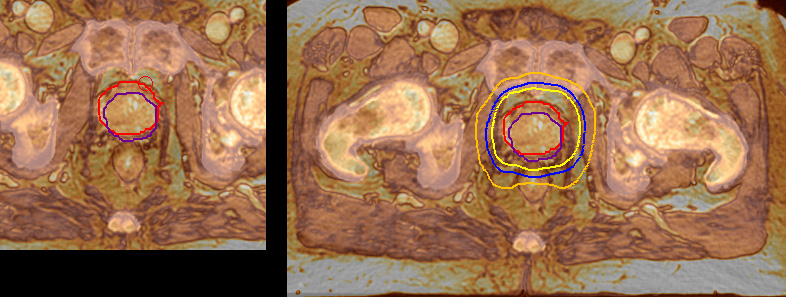

“We currently use MR-RT mainly in the abdomen and pelvis region: prostate, colorectal, pancreatic, cervical, and liver. Also in the brain, we are starting to use it,” says Dr. Yan.

“Using MR, the prostate is well delineated. We quickly see the edges of cancerous tumors like in prostate cancer, and as normal structures can be defined, we can optimize the treatment plan to protect these organs and their normal function. This can potentially improve the outcome. And it improves workflow as well. We can contour more quickly, confident that the tumor is going to be in the field.”

“When a patient registers, first CT simulation and MR simulation are done, followed by CT-MR registration on Pinnacle3. Then the target and normal organ delineation is performed on MR images. Meanwhile we create a reference CT image for online treatment and localization correction. During the treatment phase we can perform additional MRI scans to visualize the anatomy changes and create an adaptive plan. This plan basically adapts the treatment plan to the changes.”